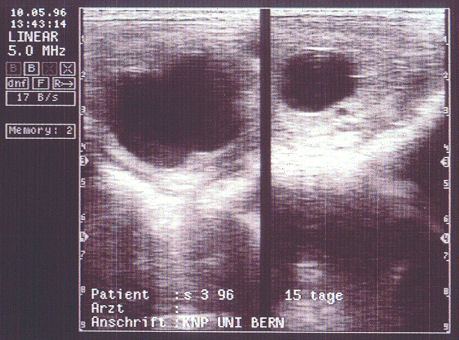

Im Anschluss an unseren April-Scherz haben wir ein Mail mit Absender aus der Uni Bern bekommen - mit einem Ultraschallbild von echten Drillingen in einem Stutenbauch.

Drillinge(!): Links zwei Fruchtblasen unmittelbar nebeneinander, rechts eine dritte (UniBE)

In der Praxis ist Mehrfachträchtigkeit bei Pferden unerwünscht - da es häufig zu grösseren Problemen kommt. Gemäss Dr. Hanspeter Meier von der Uni Bern enden etwa 65% aller Zwillingsschwangerschaften beim Pferd mit Aborten und Totgeburten, und in den restlichen Fällen sind die neugeborenen Fohlen meistens klein und zeigen Exterieurmängel. Praktisch jedes zweite überlebt gemäss dem Zuchtexperten (altes und neues VSV-Vorstandsmitglied) die ersten Lebenstage nicht.